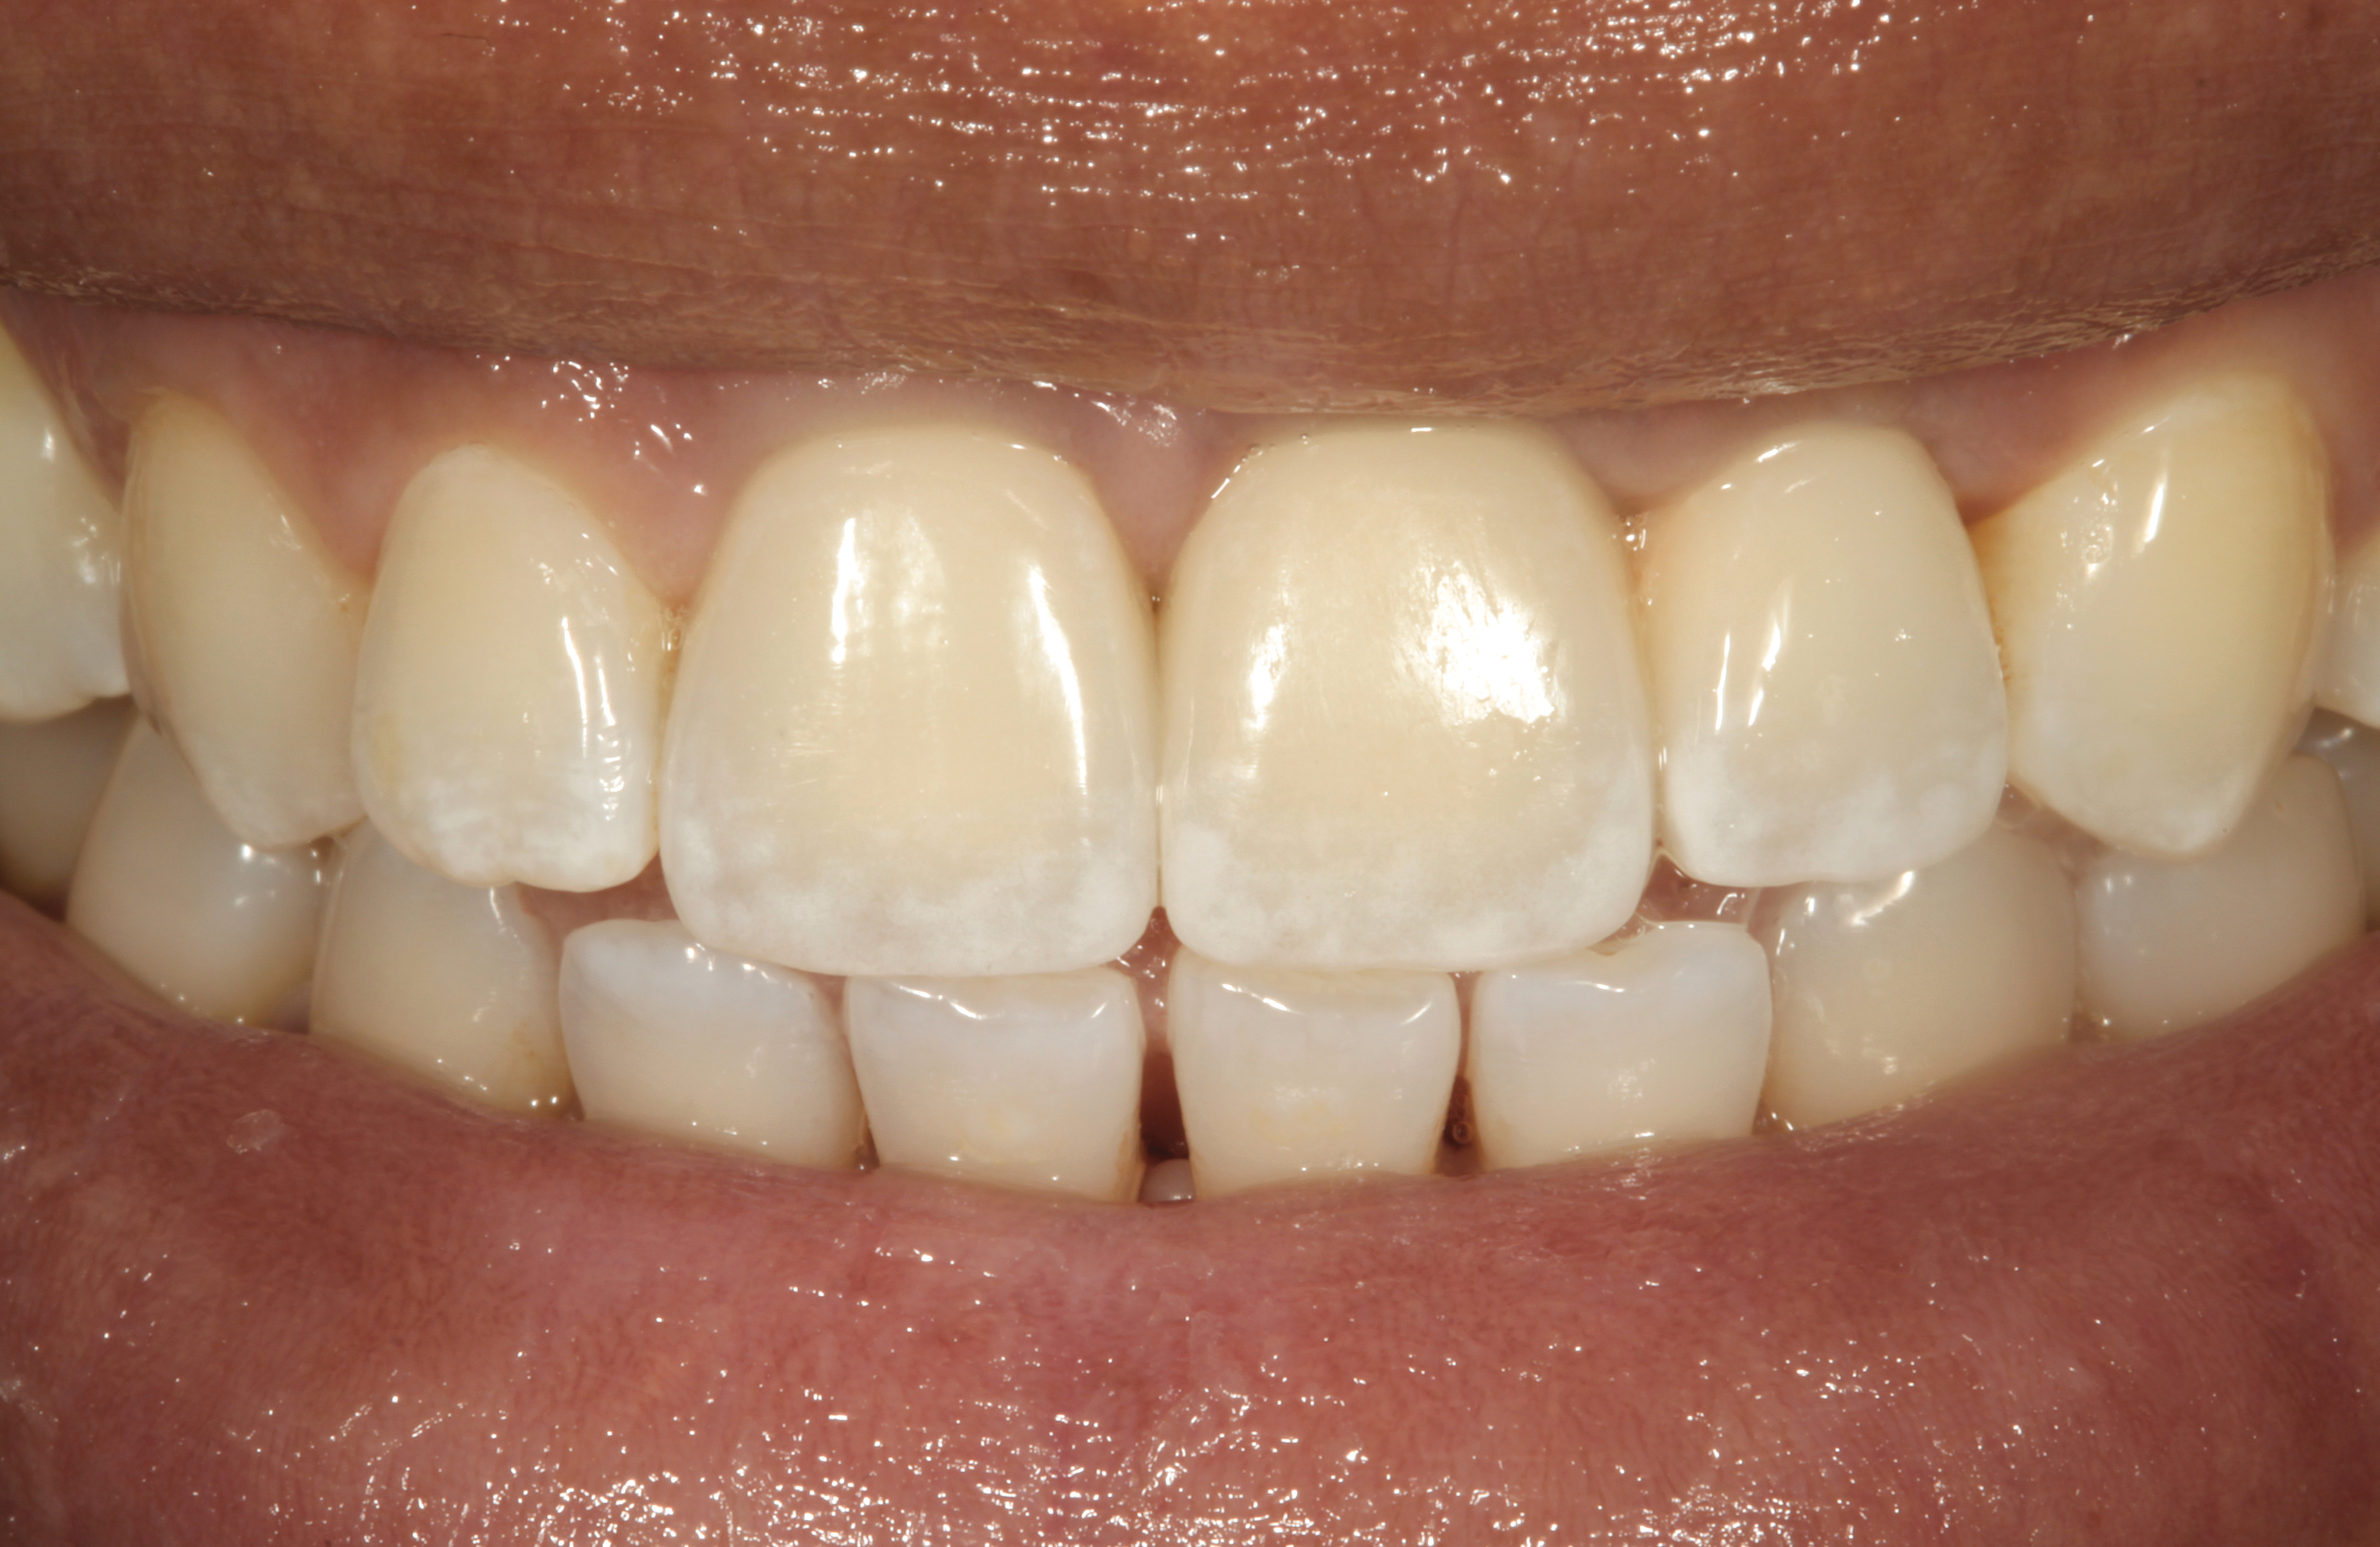

Fig 14. The extraoral smile view of the esthetically satisfied patient at 4 years recall.

Figure 14

It was determined that additional augmentation was required to increase the soft-tissue volume, so a subepithelial connective tissue graft was acquired from the palate (Figure 8),23,24 placed, and allowed to mature for at least 3 months. Second-stage implant undercovering surgery with a palatal-biased incision was performed after tissue maturation to further thicken the labial soft tissues. In addition, a flat contoured healing abutment was placed to allow the soft tissues to mature without risk of recession, and the RBR replaced (Figure 9). After 4 to 6 weeks of healing, a flat contoured screw-retained provisional restoration was inserted (Figure 10) with the proper submergence profile to restoratively sculpt the soft tissues. An implant-level impression was made and the definitive cement-retained metal-ceramic restoration fabricated and inserted (Figure 11 through Figure 13). The final esthetic outcome to restore the proper length and proportion of the right lateral incisor to match that of the contralateral incisor was accomplished using the treatment steps outlined above, where the mucosal tissues were augmented after implant decoronation (Figure 14).